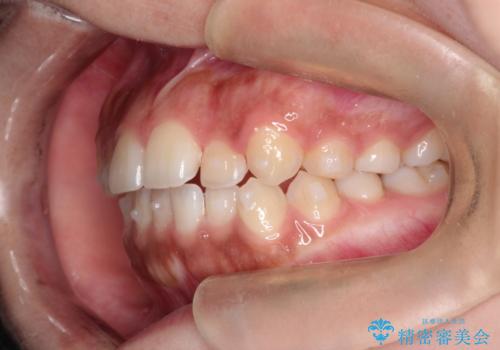

インビザライン 前歯のがたつきを目立たず矯正

- 前歯のがたつきが気になるとのことで来院されました。

インビザラインにて治療を行いました。

わずかに歯と歯の間に隙間を作り、歯列矯正を行いました。

マウスピースをしっかりと使用していただけたので、スムーズに治療を終了することができました。